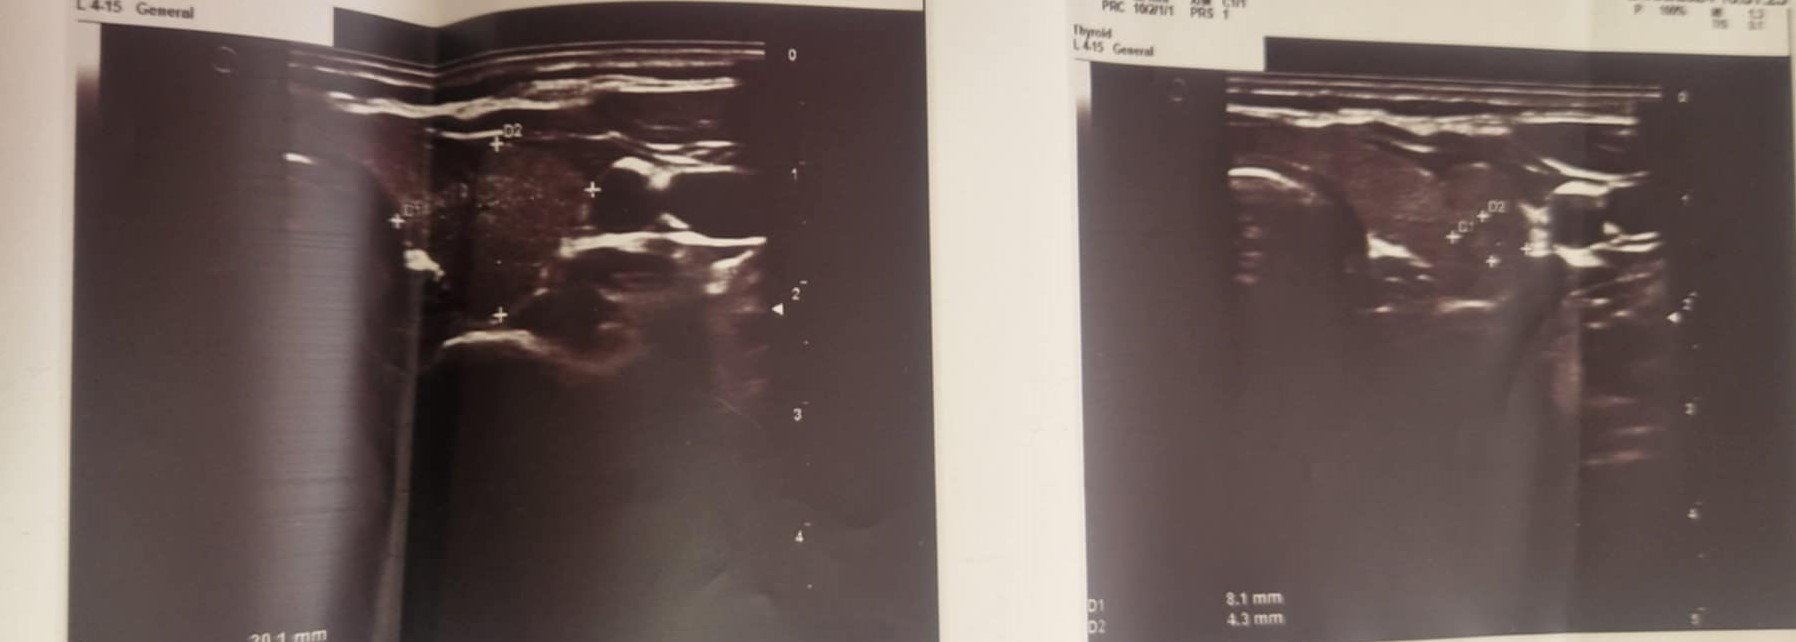

Ехографията показа и възел вляво.

Пих Сарита 3 месеца и след биопсия излязоха следните резултати

Нормално ли е всичко, трябва ли оперативна намеса, да продължавам ли със Саритата ? Благодаря ви.